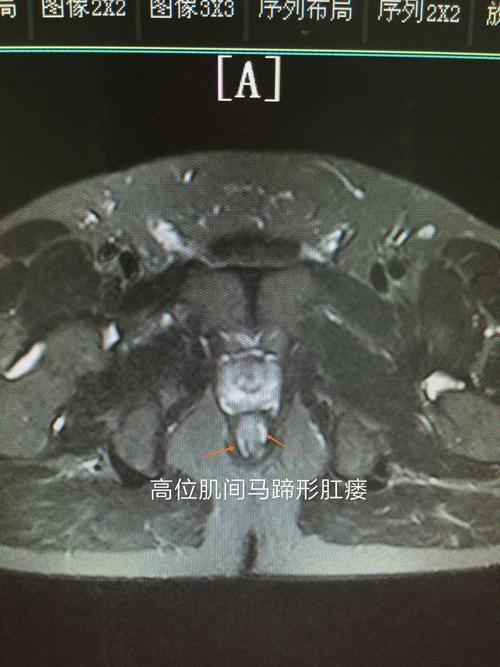

手术案例:高位肌间马蹄形肛瘘行tropis 肛管后间隙切开一例

高位马蹄形肛瘘

马蹄形肛瘘

马蹄形肛瘘图片

马蹄形肛瘘示意图

马蹄形肛瘘图片图解

马蹄形肛瘘手术图片